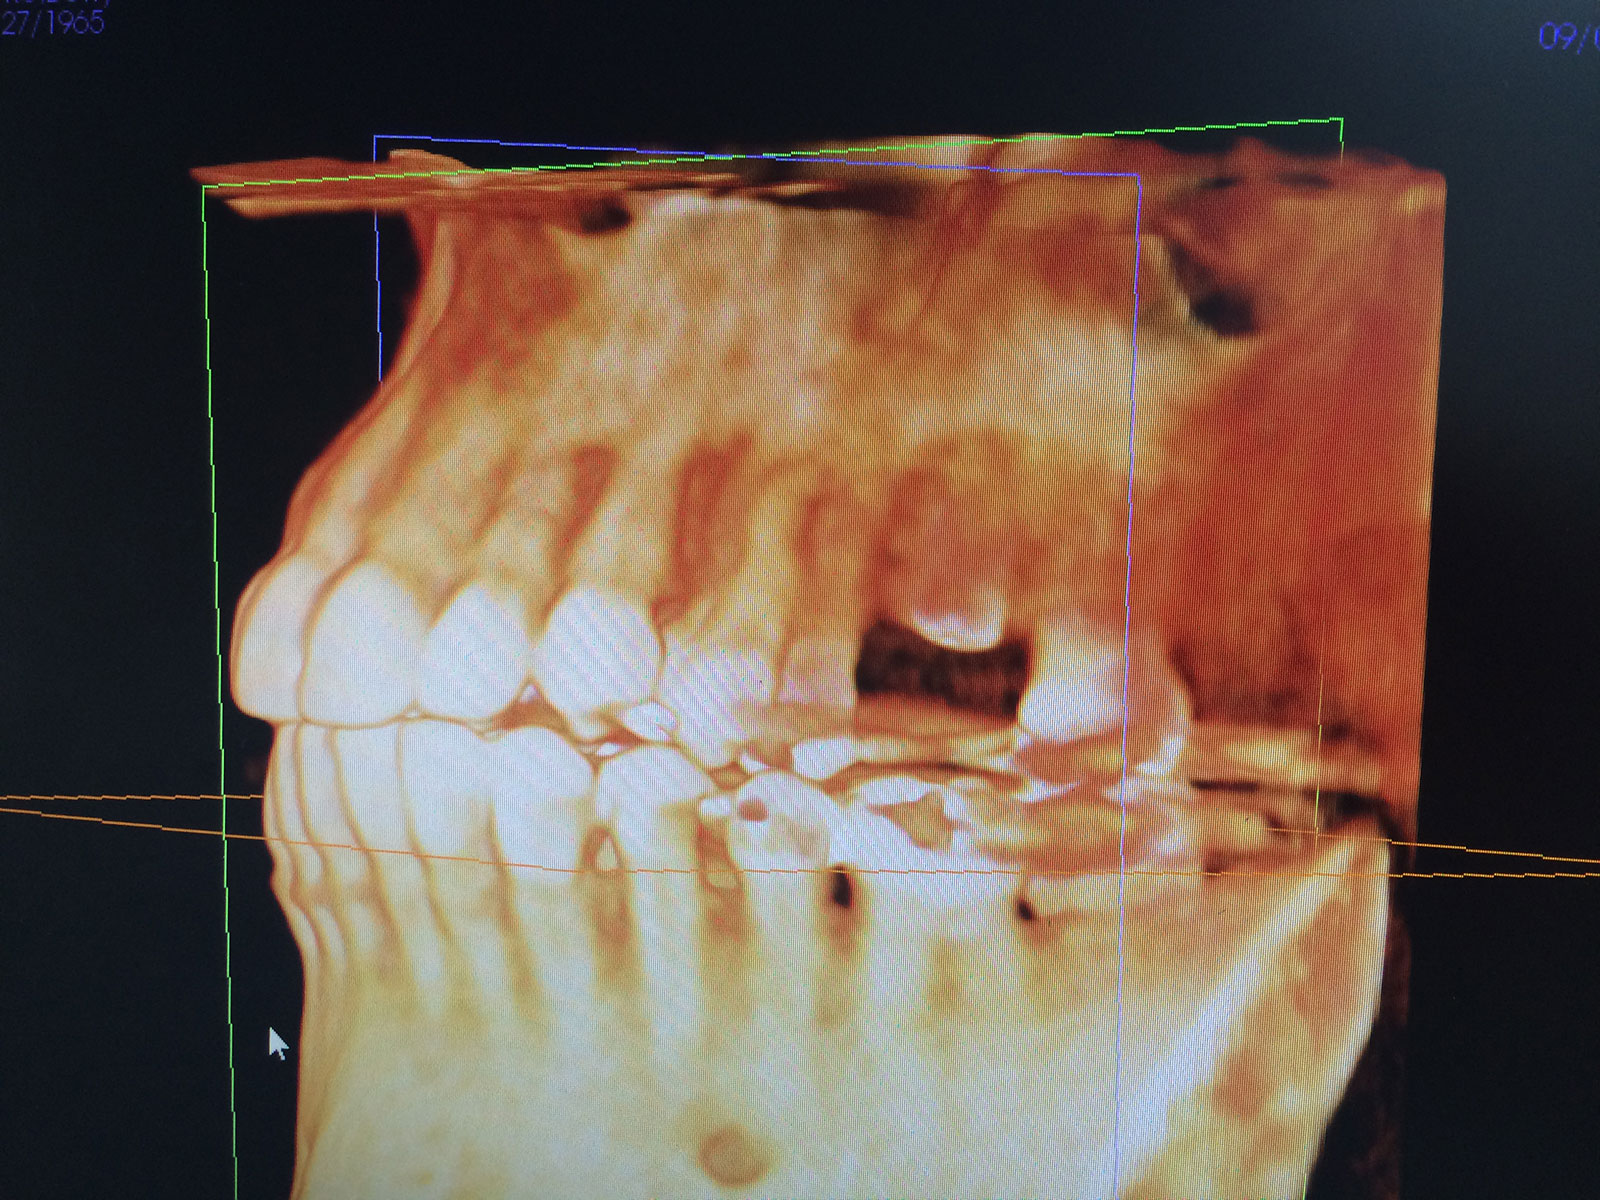

Sinus Grafting Procedures

A sinus grafting procedure, also known as a sinus augmentation, is for patients who have insufficient natural bone in the areas where dental implants are needed. They are long lasting, strong and sturdy, and fit and function like natural teeth. The procedure involves adding bone, either your own natural bone from another part of the body, from a donor or made of processed or synthetic bone material, and placing it below the sinus so that the implants can be placed. After the bone has healed and developed, usually around four to 12 months, the dental implants can be placed.

The photos on this website are from real surgeries performed by Dr. Ulloa. Due to the

graphic nature of the images and content, viewer discretion is advised.